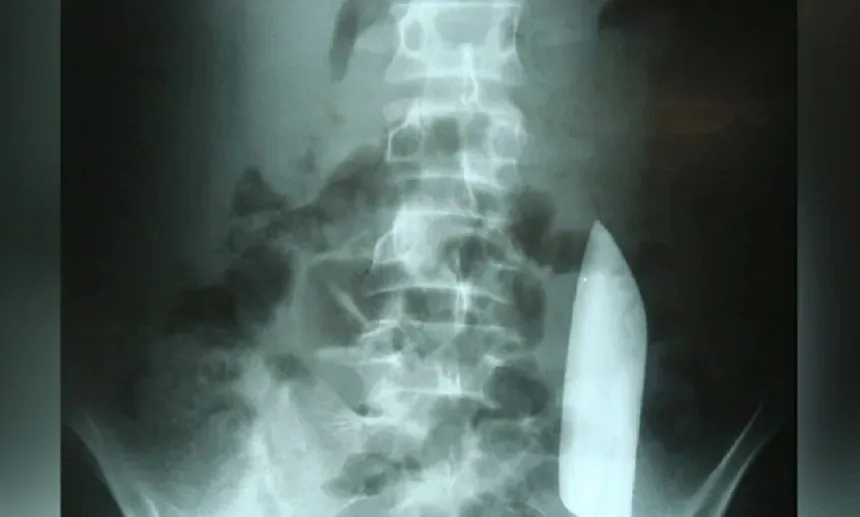

Unable to determine the cause of the infection, doctors ordered an X-ray and were shocked to see a large knife lodged in the man’s chest.

“Initial imaging with a lateral chest radiograph demonstrated a retained metallic object in the mid-thorax, with surrounding opacification likely representing a resolving or chronic loculated haematoma or post-traumatic fibrosis, a sequela of the patient’s stab wound,” doctors wrote in their case study.

Somehow, the knife, which had entered through the right scapula, miraculously did not hit any major organs.